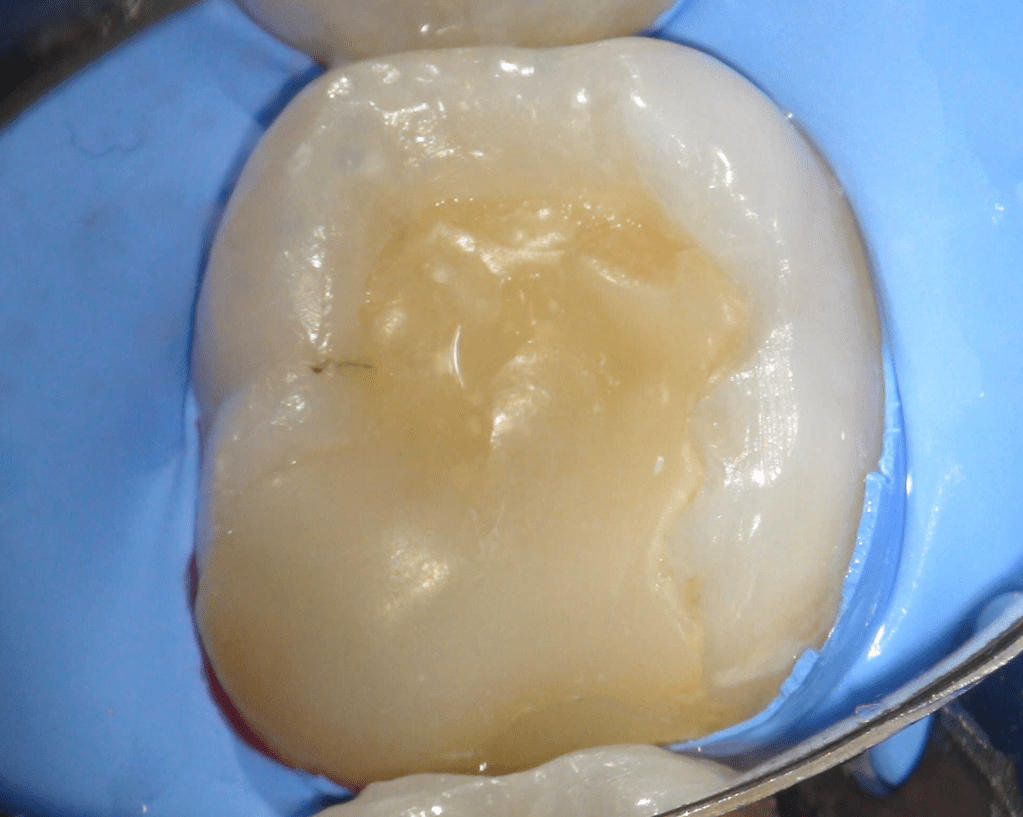

Pulpotomía biodentine + reco preendio